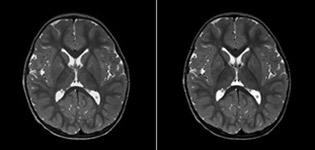

Philips mDIXON TSE is a two-point DIXON technique that separates water and fat signals, for time-efficient fat-free imaging, even in challenging neuro anatomy. “mDIXON TSE has been one of the most significant improvements in imaging sequences that we have utilized to date at PCH,” says Dr. Miller. “Its multi-parametric acquisition allows us to obtain fat suppressed images and equivalent non-fat suppressed T2 images all in the same sequence. In addition, prior methods of fat suppression could be artifactually corrupted by poor patient anatomy or poor operator application, but with mDIXON we now have a robust and reliable method of fat suppression.” Fat saturation is historically challenging at the ends of fields of view, especially in total spine imaging and in difficult patient anatomy such as the lower regions of the neck. “Due to the unique fat suppression capabilities of mDIXON, however, these challenges no long apply,” says Dr. Miller. “We routinely obtain homogeneous fat suppression under virtually all conditions. It has also led to some efficiencies by not having to repeat sequences because of that technical failure.”

“mDIXON TSE has increased our diagnostic confidence in ruling in or ruling out abnormalities in which fat suppression is critical to diagnosis, such as metastatic disease or osseous abnormalities.”

“mDIXON TSE is most useful in patients with lesions or abnormalities in the soft tissues such as the face and neck, and for patients with contrast enhancing abnormalities that are mostly visible with fat suppression,” says Dr. Miller. “All our spine imaging now routinely contains mDIXON water-only T2 images, and this allows us to identify pathology that may be obscured by non-fat suppressed imaging such as injuries of the bone. And it’s not necessary to obtain additional standard TSE T2 images because the in-phase mDIXON images are equivalent to standard TSE T2 images.”